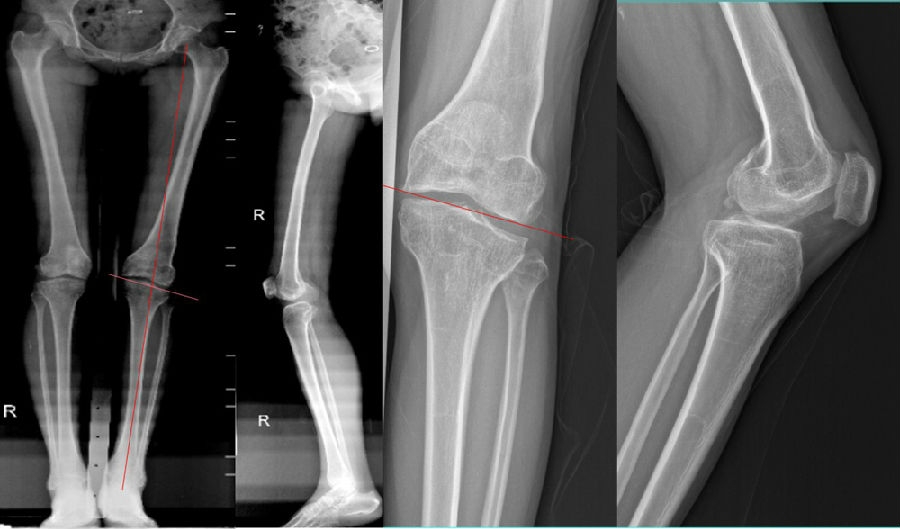

术前MR

该病例特点:患者中年女性,49岁,较活跃;JLCA基本正常,关节线倾斜,下肢力线略外翻;倾斜来源股骨内翻和胫骨外翻;既往股骨远端手术史;陈旧性软组织疤痕,局部畸形,骨质硬化,合页易骨折。

双下肢关节外畸形(畸形来源于股骨侧及胫骨侧)——LDFA100°*MPTA:102°

软骨磨损的程度——内外侧局部软骨均有磨损,外侧明显。